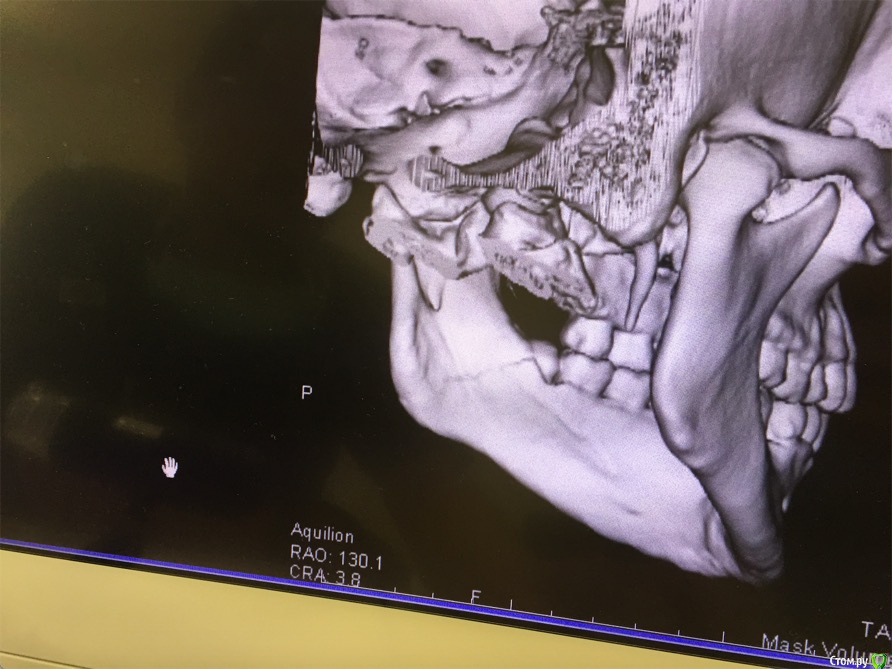

cinovka Опубликовано 10 сентября, 2015 Поделиться Опубликовано 10 сентября, 2015 Здравствуйте. Помогите советом. 15 августа получил перелом нижней челюсти с левой стороны в районе 7-8го зуба.25 числа наложили титановую пластину на место перелома и зашинировали. 3 сентября сняли шины. Разрез делали в ротовой полости и снаружи, для закрутки шурупов.Наружную рану опять вскрыли 1го сентября, т к началось нагноение. Гной выходит постоянно уже 9й день. все болит. зуб мудрости лежит в десне и очень сильно болит.Прошла неделя после снятия шин, а рот также не открылся. максимально открывается на 1-1,2 см.Я нахожусь за границей и врач мой толком ничего не обьясняет.Ответьте пожалуйста на следующие вопросы : 1) Кода пройдет нагноение? И почему оно произошло? (антибиотики, повязки и полоскания постоянные). 2) Когда откроется челюсть? 3) Когда можно будет удалить лежачий зуб мудрости? Снимки номер 1,2,3,4 сделаны до операции 17 августа.Снимки номер 5,6 сделаны сегодня 10 сентября. Заранее спасибо за ответы. Жду с нетерпением. Алексей. Ссылка на комментарий

ПалСаныч Опубликовано 10 сентября, 2015 Поделиться Опубликовано 10 сентября, 2015 С колесниковым не согласен категорически. Полностью поддерживаю криокова. Это не секвестр, это наложение двух линий перелома с внутренней и наружной стороны. Если б ко мне попал пациент с такой проблемой, то я предложил бы ему такую тактику: 1 пластины снять нафиг, потому чо они там не работают, ибо наложены стнарушением правил остеосинтеза, а так же потому что в ране гной; 2 во время снятия пластин через разрез задренировать рану и провести антибактериальную терапию; 3 наложить опять шины если есть подвижность отломков после снятия пластин. 4 зуб убрать вместе с пластинами. Все написанное ИМХО. 6 1 Ссылка на комментарий

Maxfac Опубликовано 11 сентября, 2015 Поделиться Опубликовано 11 сентября, 2015 + к ПалСанычу. Зуб бы удалил первым этапом, затем - пластины. Я бы еще добавил тщательную ревизию через наружный доступ: что-то симптоматика какая-то подозрительная. Надо наркотизировать, имхо. Ссылка на комментарий

kriokov Опубликовано 11 сентября, 2015 Поделиться Опубликовано 11 сентября, 2015 1. По Вашим жалобам и клинике тянет на остеомиелит, точно только очно можно2. Вам сделали оптг, аппарат ходил кругом как Вы выразились. При таком снимке, да и при выполнении снимков другими методами линий перелома кажется что две, на самом деле плоскость перелома одна (ПалСаныч выше описал)3.учитывая, что гноетечение и со стороны полости рта в обл 8 и снаружи из послеоперационной раны и отек лица держится выраженный я бы члх еще раз потревожил, не решите на месте, надо возвращаться. Имхо Ссылка на комментарий